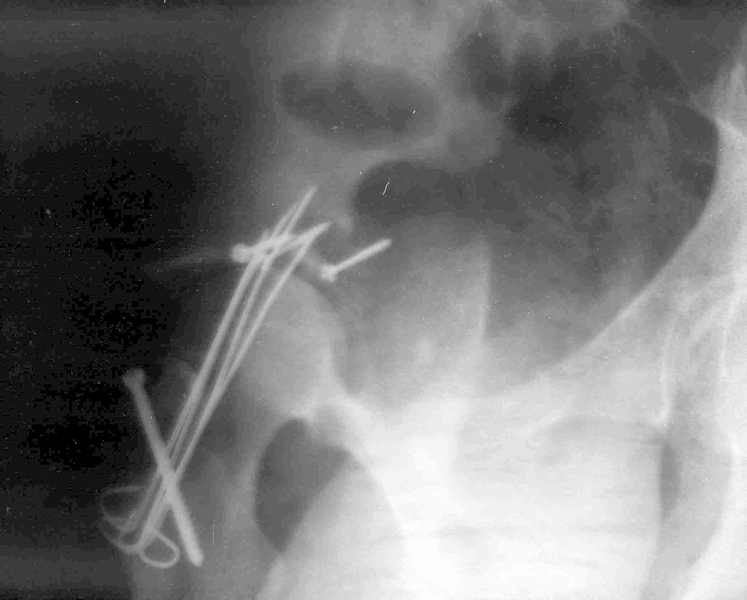

Xray1

Высылаю прямой обзорный и косой подвзошный снимки, косой запирательный неудовлетворительного качества.